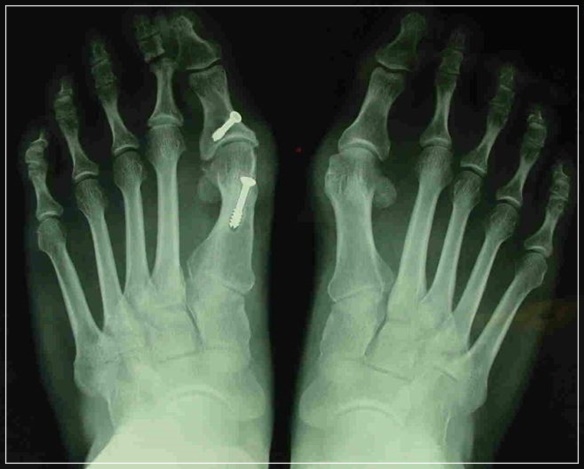

무지외반증 여부의 진단은 시진과 촉진(발가락 모양, 굳은살 등)으로 가능하지만 치료 방침을 결정하기 위해서는 방사선 검사가 필요합니다. 뼈와 뼈가 이루는 각도, 관절의 변형과 염증, 운동 범위 등을 측정합니다.

무지외반증의 치료 방법은 환자가 느끼는 증상, 변형의 심각성, 치료의 목적(염증과 통증의 조절인지, 미용적 문제까지 해결하는 것인지) 등에 따라서 달라집니다. 심하지 않은 경우 증상을 조절하고 변형의 진행을 늦추기 위해서 볼이 넓고 부드러운 신발을 신고 교정을 위한 깔창이나 보형물을 사용해 볼 수 있습니다. 심한 변형은 수술적으로 교정해야 하며 돌출 부위의 뼈를 깎아내고 인대와 연부조직의 길이를 조절합니다.

무지외반증을 적절하게 치료하지 않고 계속 좁고 높은 힐이나 발에 맞지 않은 신발을 신고 다니면 엄지발가락의 변형뿐만 아니라 관절의 염증, 다른 발가락과 발 부위의 통증과 변형, 허리의 통증 등이 생길 수 있습니다. 무지외반증 초기에는 수술하지 않고도 충분히 치료가 가능하지만 그렇지 않은 경우 증상이 더 악화되기 전 수술을 통해 교정하는 것이 좋습니다.